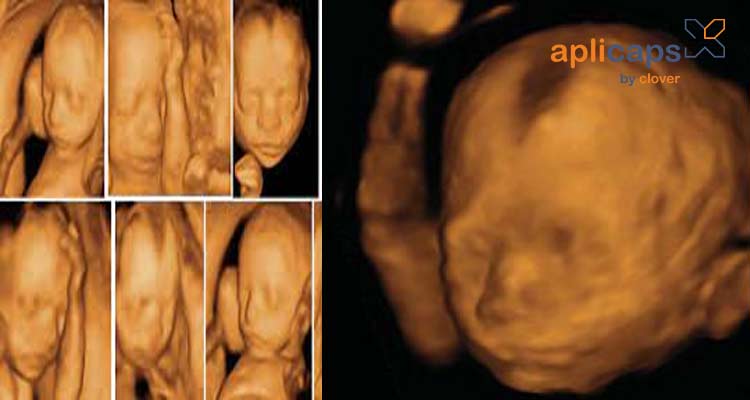

Hình ảnh siêu âm thai nhi 20 tuần khoẻ mạnh

Khi siêu âm thai ở tuần 20 mẹ có thể biết rõ hơn về em bé của mình có đang phát triển khỏe mạnh không. Bác sĩ thông qua siêu âm sẽ kiểm tra được tất cả bộ phận của thai nhi và các chỉ số cần thiết.